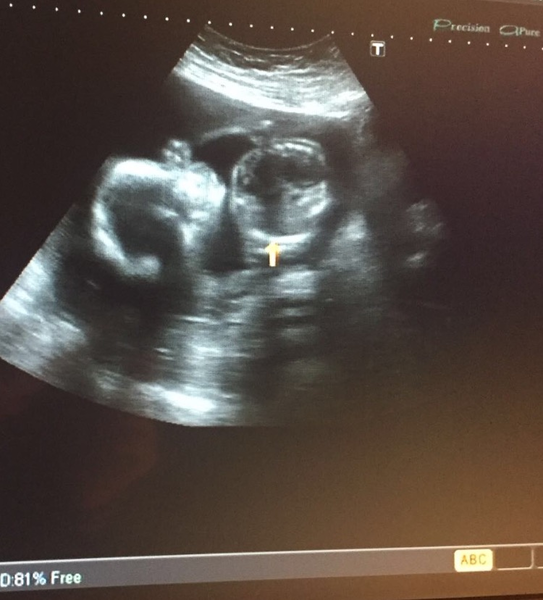

Had my scan today, all is well with the baby!!! Chuffed to bits!!

Have to go back for a scan at week 34 as have a low lying postier placenta. Edge is just at the cervix but said it usually moves up. Hopefully does as really don't want a c section.

Back from my scan. All was well but took good part of an hour as the wriggler kept wriggling. It's a boy! DP and I are mildly shocked as we were sure it was a girl. It's going to be busy here with two boys.